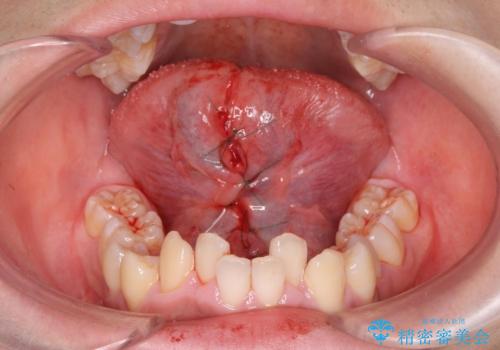

- 滑舌が悪いとの事で来院。

当日に舌小帯の切除を行う事になりました。

手術は当日に行う事ができ、一週間後に抜糸を行います。